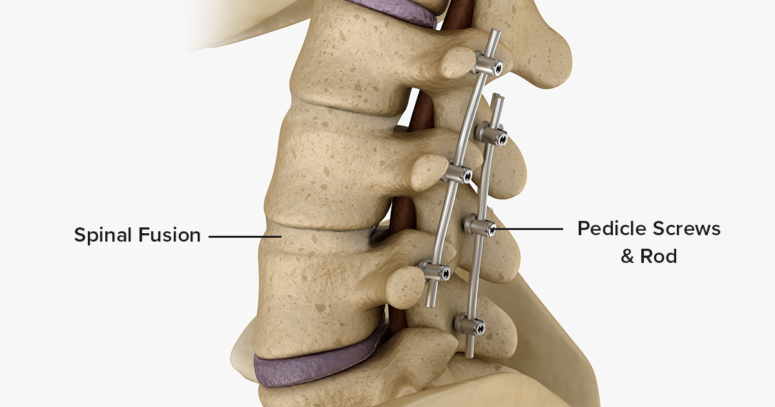

Surgical treatments

Surgery may be considered in more severe cases, particularly when:

The curvature is pronounced and continues to worsen.

Pain or neurological symptoms significantly impact daily life.

Breathing or organ function is affected by the spinal deformity.

The most common procedure is spinal fusion, where vertebrae are stabilised using rods, screws, and bone grafts to correct and support the curve.

The decision to proceed with surgery is made on an individual basis, taking into account the severity of the curve, overall health, and patient goals.